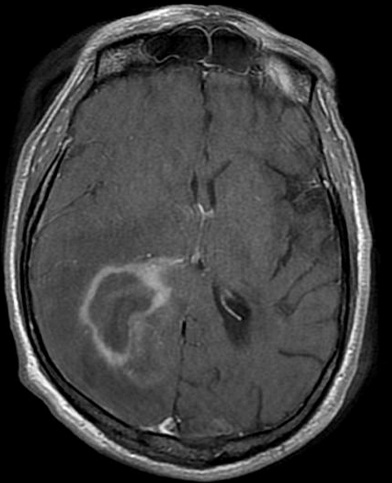

Glio: The CT/MRI findings of a butterfly appearance with central necrosis is classic for GBM, and the heterogenous, serpiginous contrast enhancement is typical of high-grade.

This patient has a primary CNS lymphoma. The presence of EBV DNA in the CSF is specific for this condition. MRI reveals a weakly ring-enhancing mass that is usually solitary and periventricular.

Toxoplasmosis is a good differential diagnosis; however, it is unlikely in this patient since he is receiving trimethoprim-sulfamethoxazole. MRI reveals multiple, ring-enhancing, spherical lesions in the basal ganglia. A positive Toxoplasma serology is quite common in normal subjects in the United States, and is therefore not specific for toxoplasmosis.